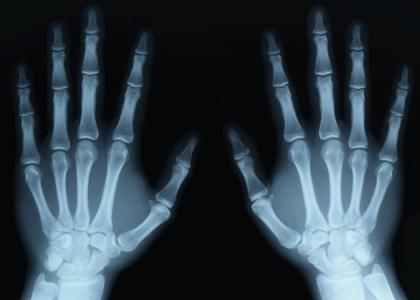

Rontgen atau X-ray merupakan prosedur medis yang menggunakan radiasi elektromagnetik untuk menghasilkan gambar bagian dalam tubuh.

Rontgen dilakukan dengan sebuah mesin khusus yang memancarkan sejumlah kecil radiasi pengion. Perangkat khusus akan menangkap gambar atau foto bagian organ tubuh yang ditembakkan radiasi pengion.

Jumlah radiasi yang digunakan rontgen ekstremitas untuk memindai tangan dan kaki lebih besar dibandingkan dengan rontgen dada.